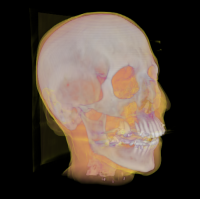

Erkennung der Substrukturen des Acetabulum in 3D-Pelvis Modellen

Für die Planung von Hüftoperationen ist eine genaue Analyse der patientenindividuellen Geometrie erforderlich. Dabei ist vor allem die Oberflächenstruktur der Hüftpfanne (Acetabulum) als Kontaktregion zum Femurkopf von besonderem Interesse. Betreuer: Karl-Ingo Friese Mai 2015